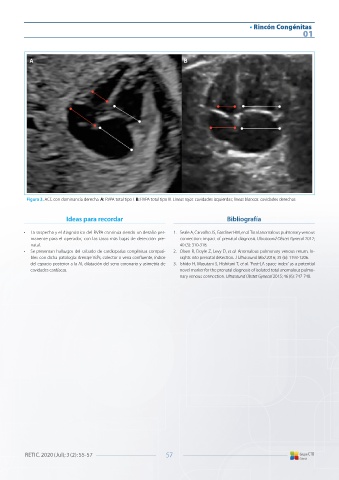

Figura 3. ACC con dominancia derecha. A: RVPA total tipo I. B: RVPA total tipo III. Líneas rojas: cavidades izquierdas; líneas blancas: cavidades derechas